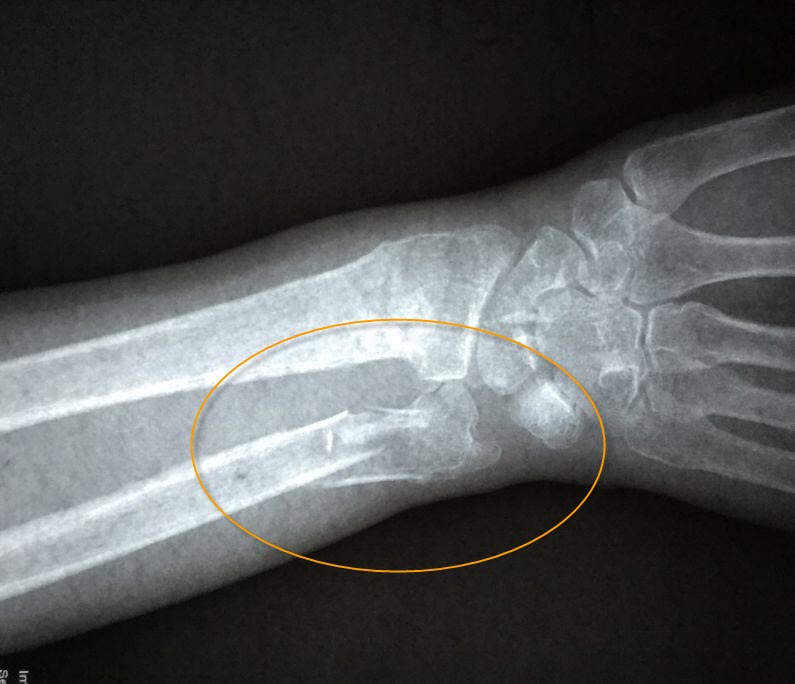

二月十三日,老人在积水潭医院复查拍片时,医生发现老人骨折处竟基本长愈,如图3。医生表示:老人家这个年纪了,一般都骨质疏松,半个月的时间,要想愈合到这种程度,就是年轻人,也是不容易的。并且说:老人的恢复情况确实很好。

'图3'

图3

老人及家人看到底片,都很开心,连说“没想到”、“真是奇迹”。